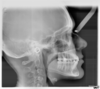

Les radios avant le traitement